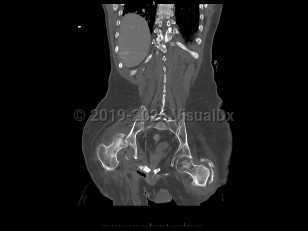

Septic arthritis

An infection of a joint most frequently caused by bacteria (although fungi, parasites, and mycobacteria may also rarely cause this infection).

This infection occurs most commonly as a result of hematogenous seeding of the joint in the setting of bacteremia. A joint may be inadvertently inoculated with a pathogen at the time of surgery or trauma. In some patients, a severe soft tissue infection may spread to involve a nearby joint.

Patients present with a swollen, warm, stiff, and painful joint. Fever may be present. The majority of the time, a single joint (usually the knee) is involved. Symptoms develop over 1-2 weeks. If the infection is caused by N gonorrhoeae, patients classically also present with a rash and tenosynovitis. If the infection is due to fungi or mycobacteria, the symptoms may be subtler and may worsen more gradually.

Diagnosis can be made by arthrocentesis. Joint fluid should be sent for analysis including cell count, microscopic analysis for crystals, Gram stain, and bacterial culture. Additional cultures of the joint fluid can be obtained if an atypical pathogen is suspected by history or examination.